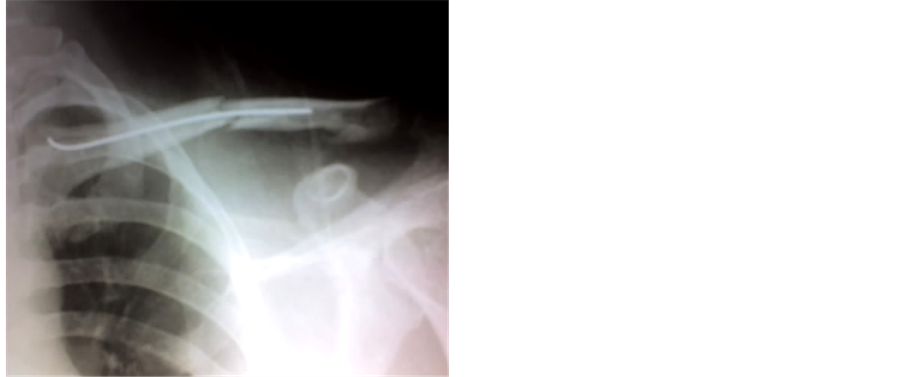

Patient was placed supine. A one cm transverse incision was taken about two cm lateral to the sterno-clavicular joint. A drill hole was made into the anterior cortex using a 2.7 mm drill bit and the medullary canal was entered using awl. A preselected size of TEN was advanced along the medullary canal unto the fracture site under image intensifier control. The fracture was reduced by closed method and the nail advanced across the fracture site into the lateral fragment. Continuous visualization under image intensifier using antero-posterior and oblique views aided advancement of the nail. The bend tip of the nail was rotated to negotiate the entry into the lateral fragment. The nail was advanced only when the surgeon was absolutely sure that it has engaged the lateral fragment. The medial end of the nail was bent and buried in the soft tissue to facilitate easy removal at a later date (Figure 1, Figure 2). All patients were discharged on the next day after the operation. Sutures were removed after two weeks.

Figure 1. Fracture middle third of clavicle.